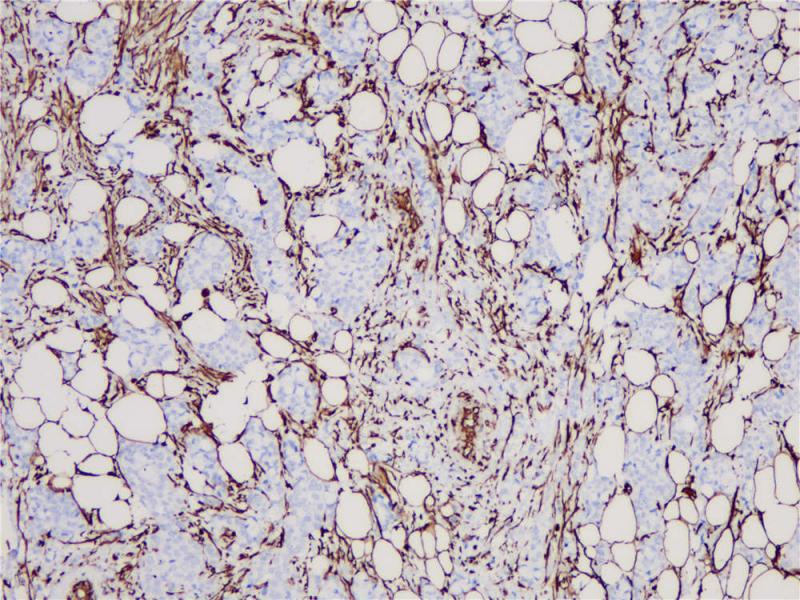

宫颈上皮内瘤变p16(BPM6238)染色

p16 INK4A(p16)是一种细胞周期蛋白依赖性激酶(CDKs)抑制剂,参与细胞周期的调控。当P16 INK4A基因发生缺失、突变等,不能抑制CDK4,最终导致细胞进入恶性增殖,加速肿瘤发生。p16 INK4A主要响应致癌基因表达、染色质断裂和各种压力胁迫等事件,这有利于受损细胞几乎无一例外地被衰老程序所捕获。因此,p16 INK4A的表达是常用的衰老细胞标志物。另外,p16 INK4A蛋白的高表达可作为宫颈癌细胞中的预测性生物标志物。

阳性对照

宫颈上皮内瘤变

亚细胞定位

细胞核